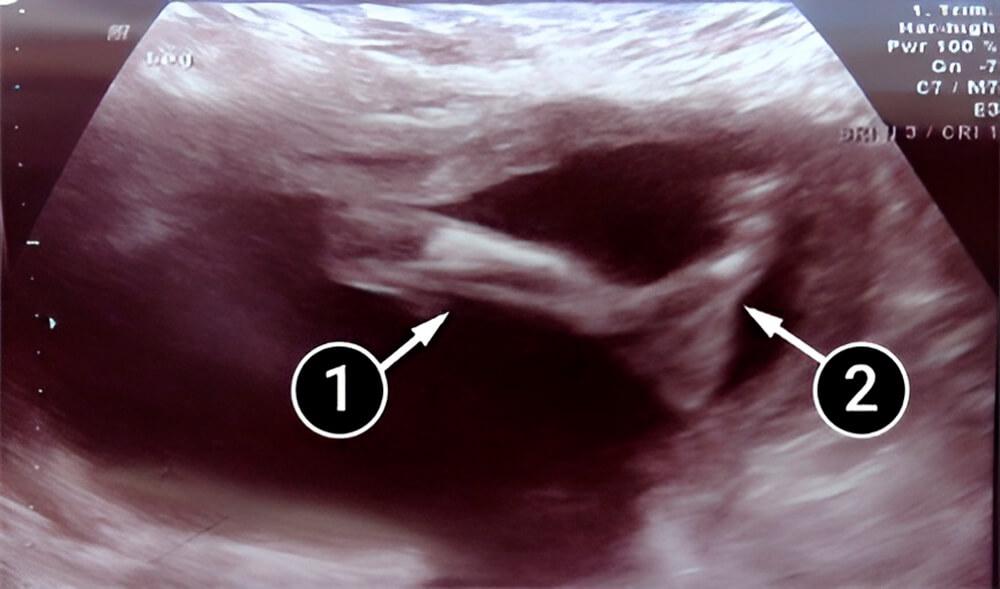

La imagen muestra la pierna del bebé. Los músculos y huesos tanto de la pierna como del pie están claros; podemos ver el arco, el talón y los dedos.